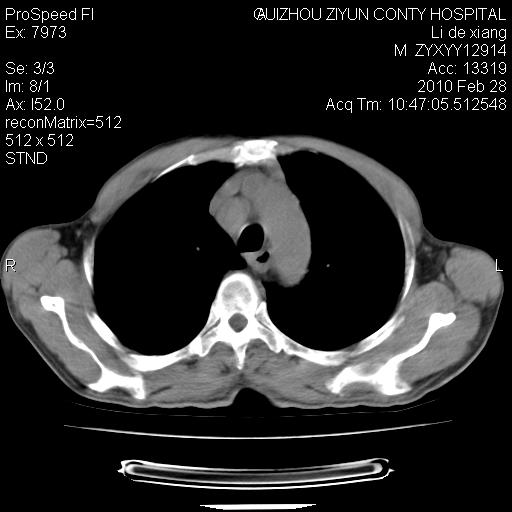

标题: CT24776:男 71Y 咳嗽咳痰胸痛两月,伴声音嘶哑。 [打印本页]

标题: CT24776:男 71Y 咳嗽咳痰胸痛两月,伴声音嘶哑。

纵膈淋巴结肿大 不除外占位性阻塞

左侧中央型肺癌伴左肺上叶阻塞性肺炎及节段性不张可能性大,建议纤支镜检查!纵隔淋巴结转移.

左侧中央型肺癌伴左肺上叶阻塞性肺炎及纵隔淋巴结转移。

左上叶支气管狭窄,阻塞性病变,肺门肿块,纵隔及肺门淋巴结增大,中央性肺癌

左肺中央型肺癌并阻塞性改变、纵膈 淋巴结转移

左侧中央型肺癌伴左肺上叶阻塞性肺炎及纵隔淋巴结转移